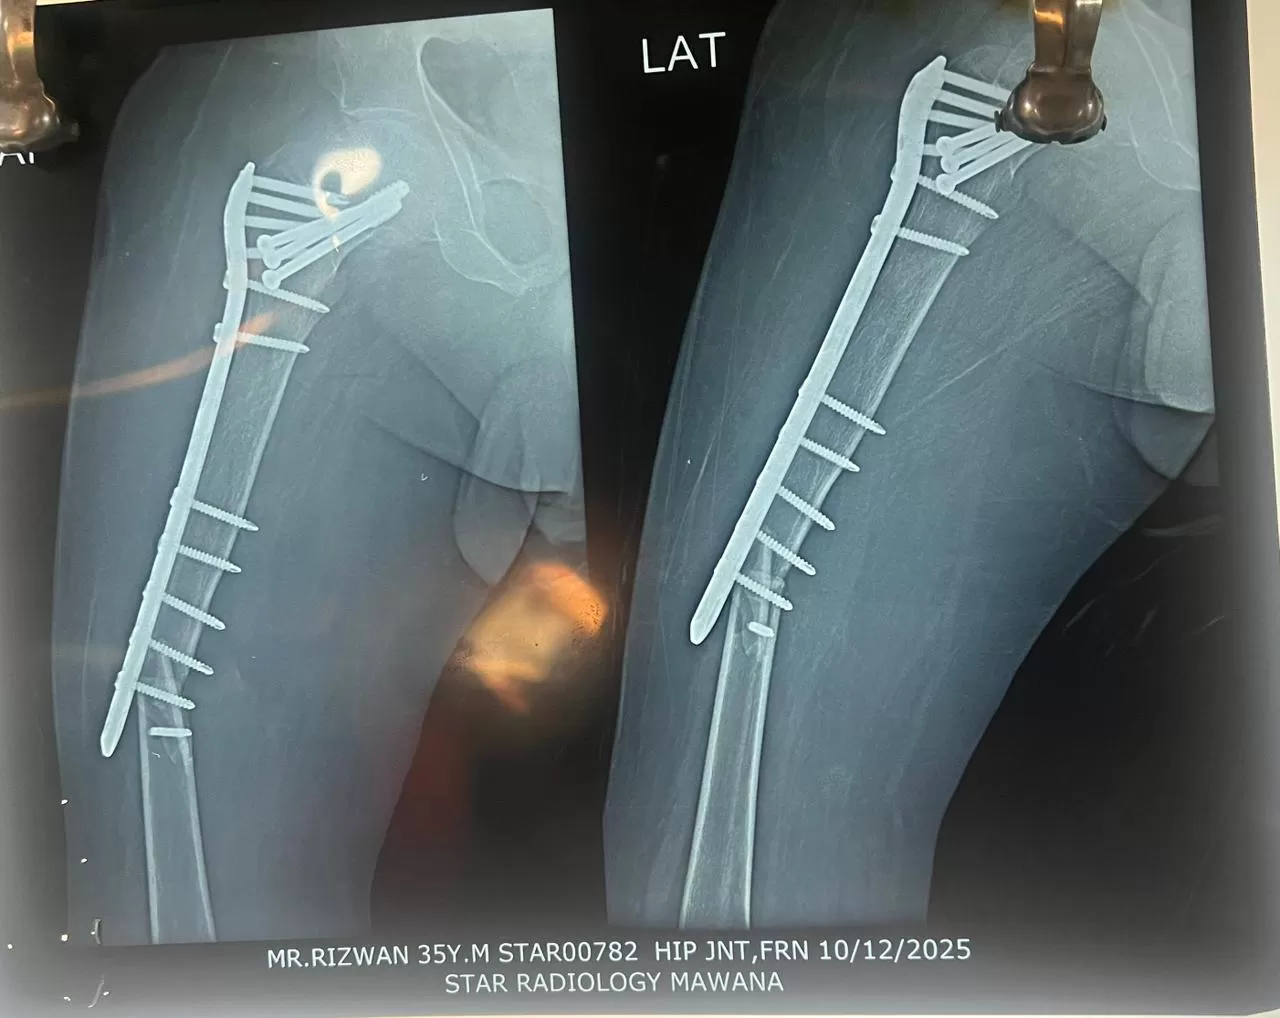

Rizwan

Name: Rizwan

Date of Operation: 13 October 2025

Age: 35 Years